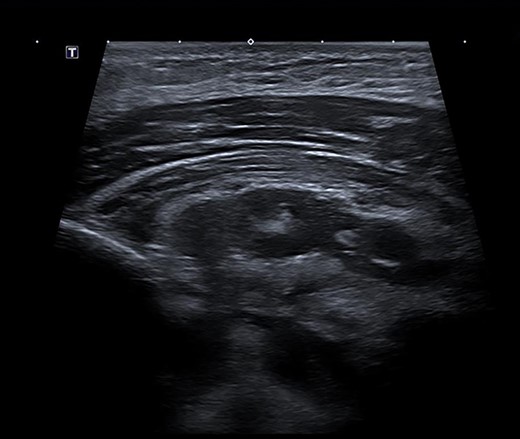

Under ultrasound guidance, two areas of collection were seen with transmitted cardiac pulsations to suggest communication with the mediastinum (Fig. 3). About 35 ml of thick pus was aspirated. The pectoral abscess grew S. aureus. Dual intravenous antibiotics were continued, with significant clinical and biochemical improvement after 1 week. The antibiotic regimen was then switched to intravenous flucloxacillin as a single agent for 4 weeks. He was discharged on day 13 of his admission.

Ultrasound scan demonstrating a retropectoral abscess communicating with the mediastinum.